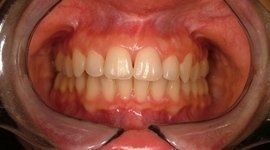

I risultati dell’ortodonzia linguale sono gli stessi di quelli ottenuti con gli apparecchi tradizionali, ma a causa della maggiore difficoltà che possono incontrare gli operatori questa tecnica è ancora usata solo da pochi specialisti in Italia e nel mondo.

Il trattamento ortodontico non rappresenta più una preoccupazione di inestetismo del sorriso durante il trattamento, ma anzi permette di apprezzarne gli avanzamenti sin dall’inizio. Il lieve imbarazzo fonetico dovuto all'interferenza dei brackets con la lingua viene superato in pochi giorni di adattamento, e solo in casi rari può richiedere fino a un mese.

I vantaggi dell’ortodonzia linguale vanno oltre l'invisibilità: consente infatti una maggiore velocità del trattamento, soprattutto nei casi con morso coperto, un minor rischio di retrazioni gengivali visibili. Garantisce un minor rischio di danni allo smalto dei denti nella superficie anteriore e una notevole efficacia nell'affrontare sintomatologie dovute a disordini e disfunzioni cranio-mandibolari.